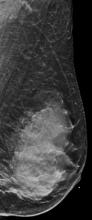

AI is also helping simplify complex tasks and help reduce the reading time on involved exams. One example of this is in 3-D breast tomosythesis with hundreds of images, which is rapidly replacing 2-D mammography, which only produces 4 images. Another example is automated image reconstruction algorithms to significantly reduce manual work. AI also is now being integrated directly into several vendors' imaging systems to speed workflow and improve image quality.

In addition to women with dense breasts, there are also other women for whom mammographic screening is not really enough, which is why research needs to continue in this field. Dr. Wendie Berg, a leading breast cancer specialist, talks with ITN about new research and advancements in breast imaging technology.

Dr. Berg, MD, PhD, FACR, FSBI, is Professor of Radiology at the University of Pittsburgh School of Medicine and Magee-Womens Hospital of UPMC, specializing in breast imaging. She is also the Chief Scientific Advisor to DenseBreast-info.org. A renowned expert, she writes and co-edits one of the leading textbooks on the topic, Diagnostic Imaging: Breast, currently in its third edition, and has co-authored over 120 peer-reviewed research publications.

Single vs. Multiple Architectural Distortion on Digital Breast Tomosynthesis

Digital Breast Tomosynthesis Spot Compression Clarifies Ambiguous Findings

AI DBT Impact on Mammography Post-breast Therapy